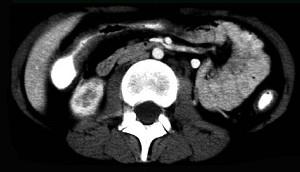

问题 女,32岁,腹痛、腹泻、便秘交替出现,黏液血便半年,里急后重,影像检查如图,最佳的诊断是 ( )

选项 A、溃疡性结肠炎 B、肠结核 C、慢性结肠炎 D、过敏性结肠炎 E、结肠癌

答案 A